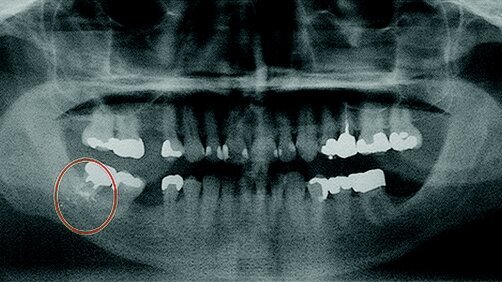

Il build-up del moncone era stato eseguito mentre i lembi erano scollati. I corpi estranei visibili nelle immagini radiografiche assomigliavano a particelle di amalgama che erano state intrappolate nella porzione apicale del lembo o nel tessuto interstiziale. L’approfondito esame orale e maxillofacciale includeva un esame intraorale ed extraorale, radiografie periapicali di tutta la dentizione e una radiografia panoramica. Tra le altre rilevazioni cliniche, la panoramica mostrava corpi estranei incidentali, simili ad amalgama, inglobati nel tessuto molle e/o duro della cavità orale a causa di un trattamento iatrogeno (Fig. 1).

La ricerca mediante CBCT dei pezzi di amalgama nella regione del dente 32 mostrava pezzi dispersi inglobati sotto la mucosa orale al di fuori del piano alveolare corticale, sia lingualmente sia buccalmente al dente 32. Si notava anche che il rapporto corona-radice del dente 32 era molto compromesso e quindi era da valutare l’eventuale estrazione dell’elemento.

Con l’i-CAT 3D CBCT, è stato utilizzato un preciso software 3D per visualizzare l’osso in tre dimensioni da diverse angolazioni (Fig. 2). Risultava che alcuni frammenti di amalgama appoggiavano sul lato buccale dell’arcata ossea sul lato destro, mentre altri frammenti poggiavano sul lato buccale dell’arcata sotto il sottosquadri linguale (Fig. 3).

Dato che non si riscontravano infiammazione e/o rimodellamento osseo, dopo un consulto tra il protesista e il chirurgo orale, i frammenti di amalgama, incidentalmente osservati in questo caso, non sono stati rimossi, in quanto non vi era alcun rischio medico o interferenza con il piano di trattamento stabilito per l’impianto nella regione del dente 30. In ogni caso, si raccomandava un costante follow-up.